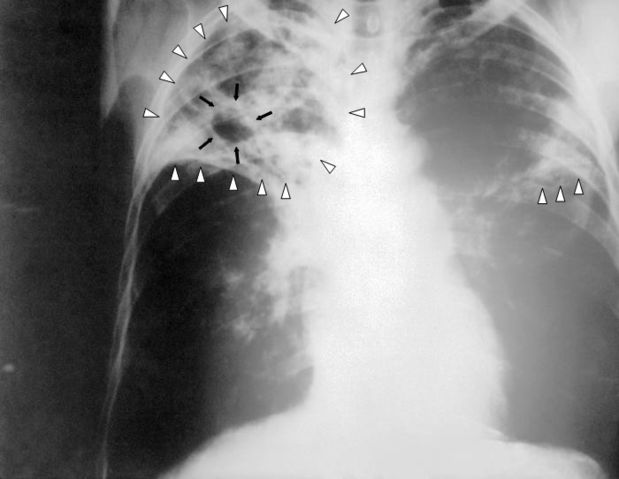

English: An anteroposterior X-ray of a patient diagnosed with advanced bilateral pulmonary tuberculosis. This AP X-ray of the chest reveals the presence of bilateral pulmonary infiltrate (white triangles), and „caving formation“ (black arrows) present in the right apical region.The diagnosis is far-advanced tuberculosis.